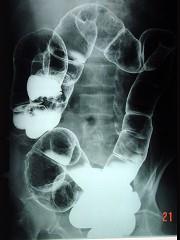

问题 男,70岁,右下腹胀,腹痛,腹泻,影像检查如图,最可能的诊断是 ( )

选项 A.结肠克隆恩病 B.结肠癌 C.结肠套叠 D.结肠结核 E.结肠淋巴瘤

答案 B